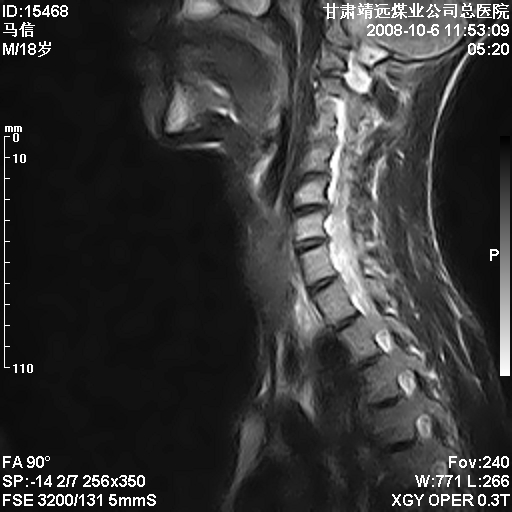

标题: MRI1827:颈椎内异常信号,是不是占位。

患者18岁,学生,在玩耍中受伤来检查,患者喜欢打篮球。颈椎内异常信号影,我们考虑占位,但是不像占位,又考虑硬膜囊的增厚,大家关建看颈椎椎管内的那个异常占位信号

腰椎的改变是不是正常发育的改变,还是打篮球的长期慢性损伤。

考虑 c3-4 c4-5 c5-6椎间盘突出,l3-4 l4-5 l5-s1椎间盘变性

后纵韧带增厚,颈2/3、3/4、4/5、5/6椎间盘变性、突出;椎体有旋转,提示椎小关节有问题;腰椎间盘变性,许莫氏结节。